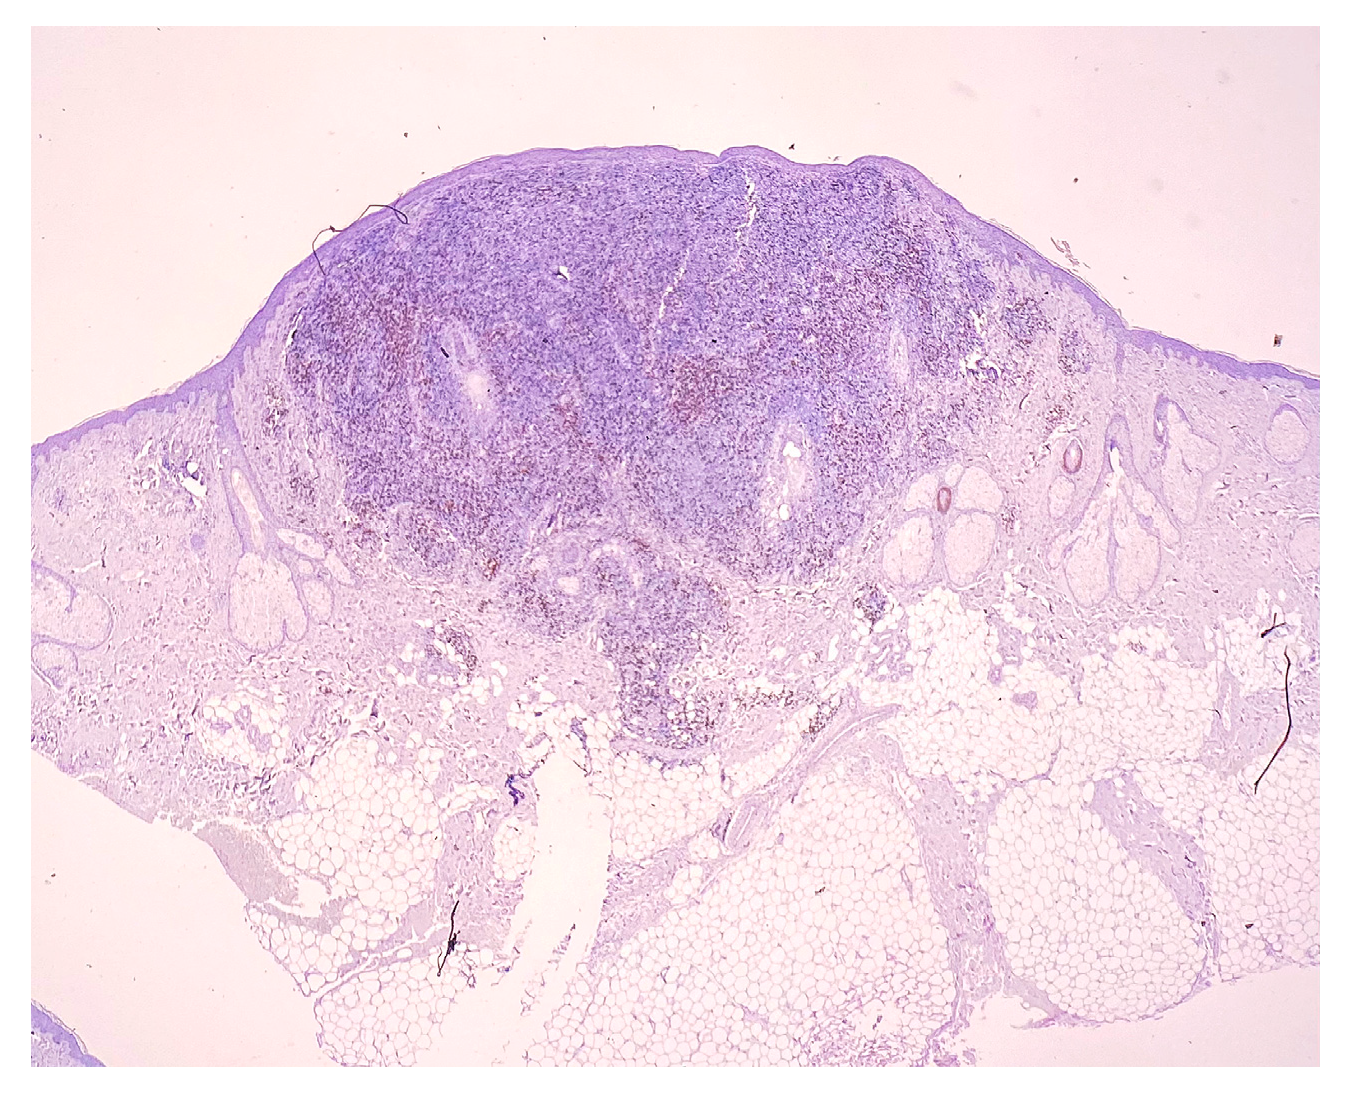

Surgical, Dermatological and Morphopathological Considerations in the Diagnosis and Treatment of Cutaneous Lymphoproliferative Tumors, Primary CD4+

2. Case Report